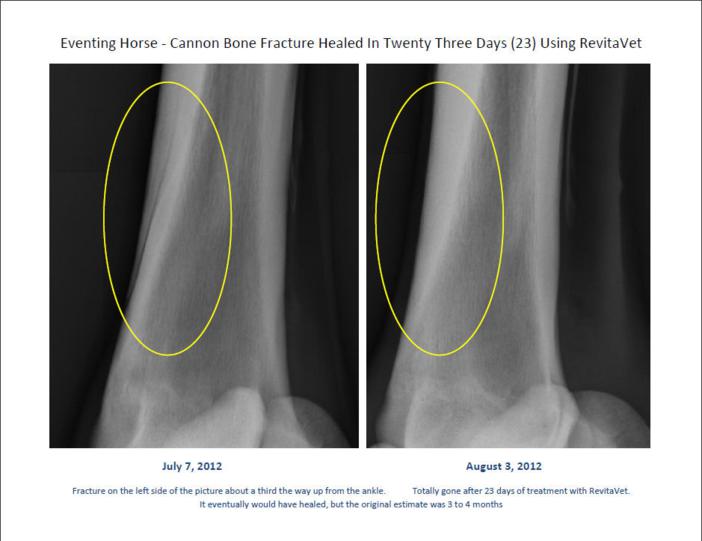

From revitavet.blogspot.com

RevitaVet How Infrared Light Helps to Heal Fractures Does Heat Help Fractures — broken bones are painful, but the majority heal very well. But there is also a third. there is limited overall evidence to support the use of topical heat in general; The secret lies in stem cells and bone’s natural ability to renew itself. the effect of heat on the healing of fractures: A widespread belief is. Does Heat Help Fractures.